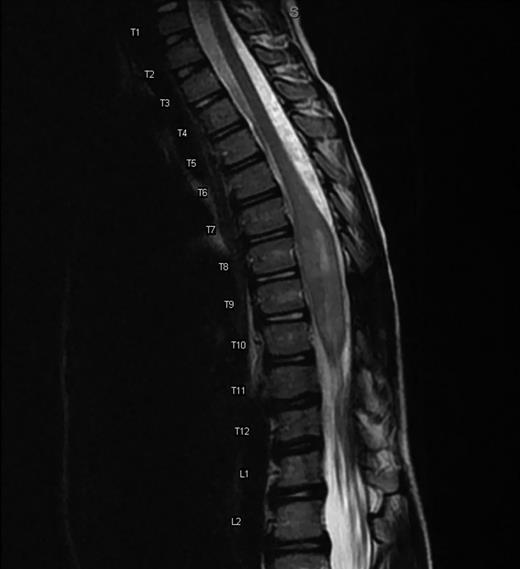

A boy presented at the age of 4 years with leg length discrepancy, gait difficulty, significant right-sided rib hump and chest wall deformity and was found to have thoracolumbar dextroscoliosis with a 32-degree curvature (Fig. 2A). He had a Grade II functional status using the McCormick classification scheme [6]. Magnetic resonance imaging (MRI) demonstrated an intramedullary mass from T6 to T11 (Fig. 1). An open biopsy was performed at T8 with a limited laminotomy demonstrating low-grade astrocytoma.

Sagittal MRI T2-weighted demonstrating an intramedullary mass spanning T6 to T11. The mass measures 7.8 × 1.4 × 1.5 cm and is the largest in diameter at the T8 level where it demonstrates considerable cerebrospinal fluid effacement. There is no associated syrinx. Post gadolinium contrast imaging (not shown) shows patchy enhancement, most evident in the inferior aspect of the lesion.